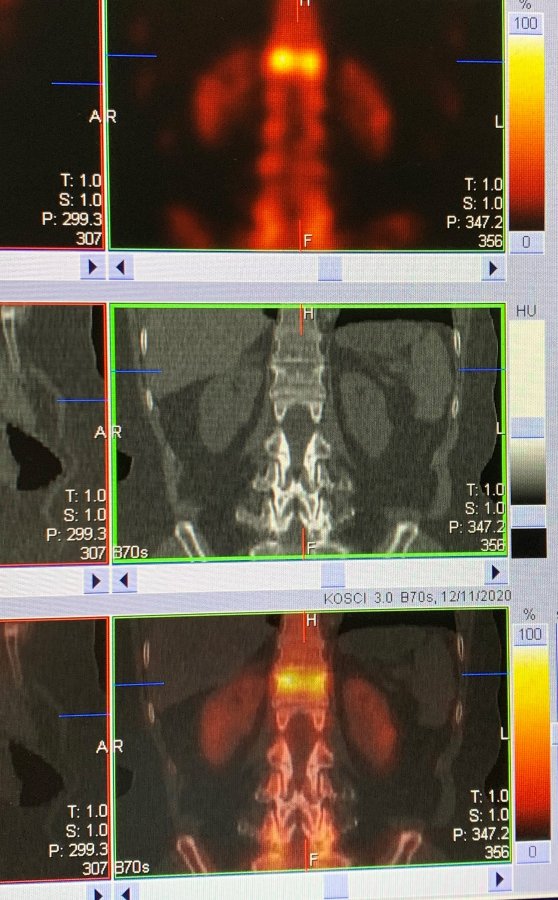

Przykładowe obrazy scyntygraficzne uzyskiwane w naszym Zakładzie Medycyny Nuklearnej: